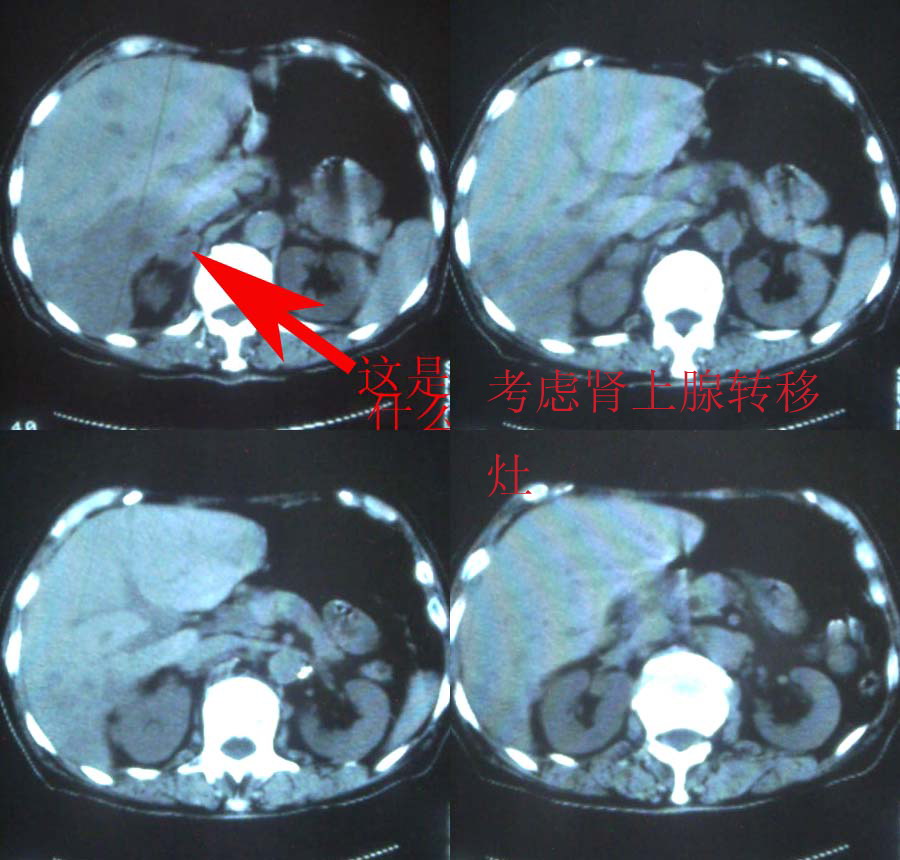

1、分析:(1)女性75岁;(2)单侧大量胸腔积液;(3)右侧肺门区团块影,单纯的压迫性肺不张?肿块?;(4)肝脏内多发结节影,大小不等,多结节型肝癌?肝癌并肝脏内转移?(5)肝脏内结节病灶中心有更低密度区;(6)右侧肾上腺不规则软组织灶;(7)肝脏各叶比例正常,脾脏不大。

2、诊断:肺癌肝脏、肾上腺转移并右侧胸腔积液。应该没问题吧?

肝脏和肾上腺转移瘤的诊断没问题,是不是肺癌转移很难说,没看见明确的肿块,胸部的片子太少了。

右下叶肝脏及右肾上腺占位,右侧大量胸腔积液伴下叶肺不张,原发部位病灶不能定。也许肝右叶为原发,也未一定。